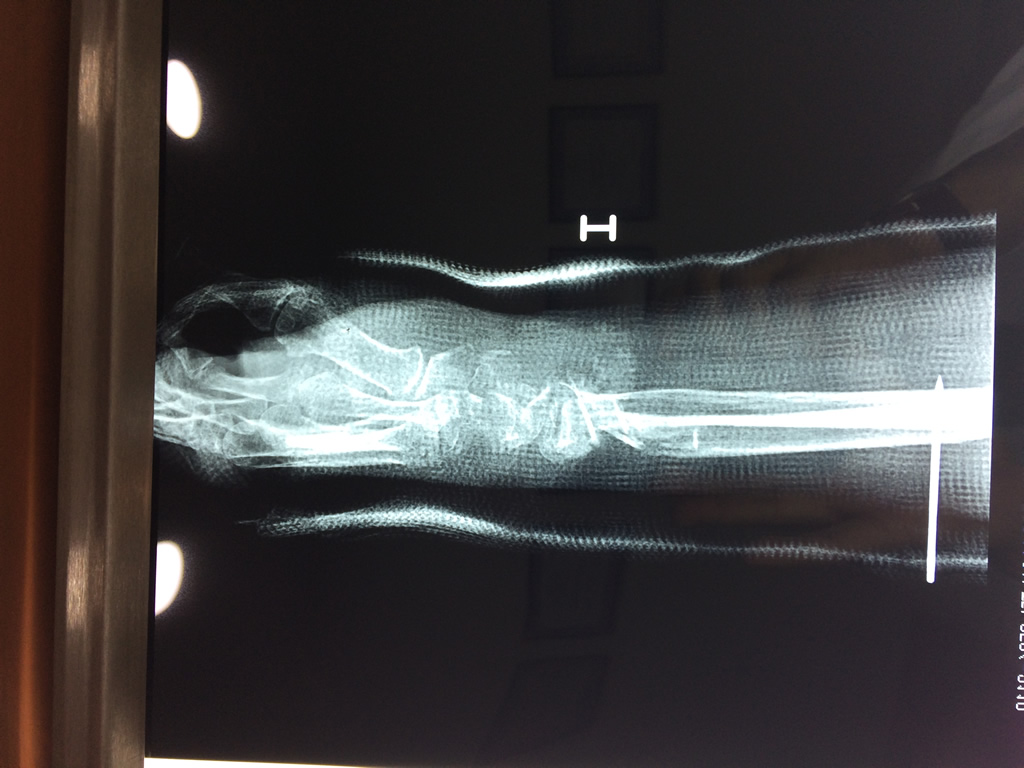

Cirugías de Húmero - Cirugías de Muñecas y Manos

Los procedimientos más comunes en cirugía de la mano son aquellos destinados a reparar traumatismos, incluyendo lesiones de tendones, nervios, vasos sanguíneos, y articulaciones; huesos fracturados; y quemaduras, cortes, y otros daños de la piel.